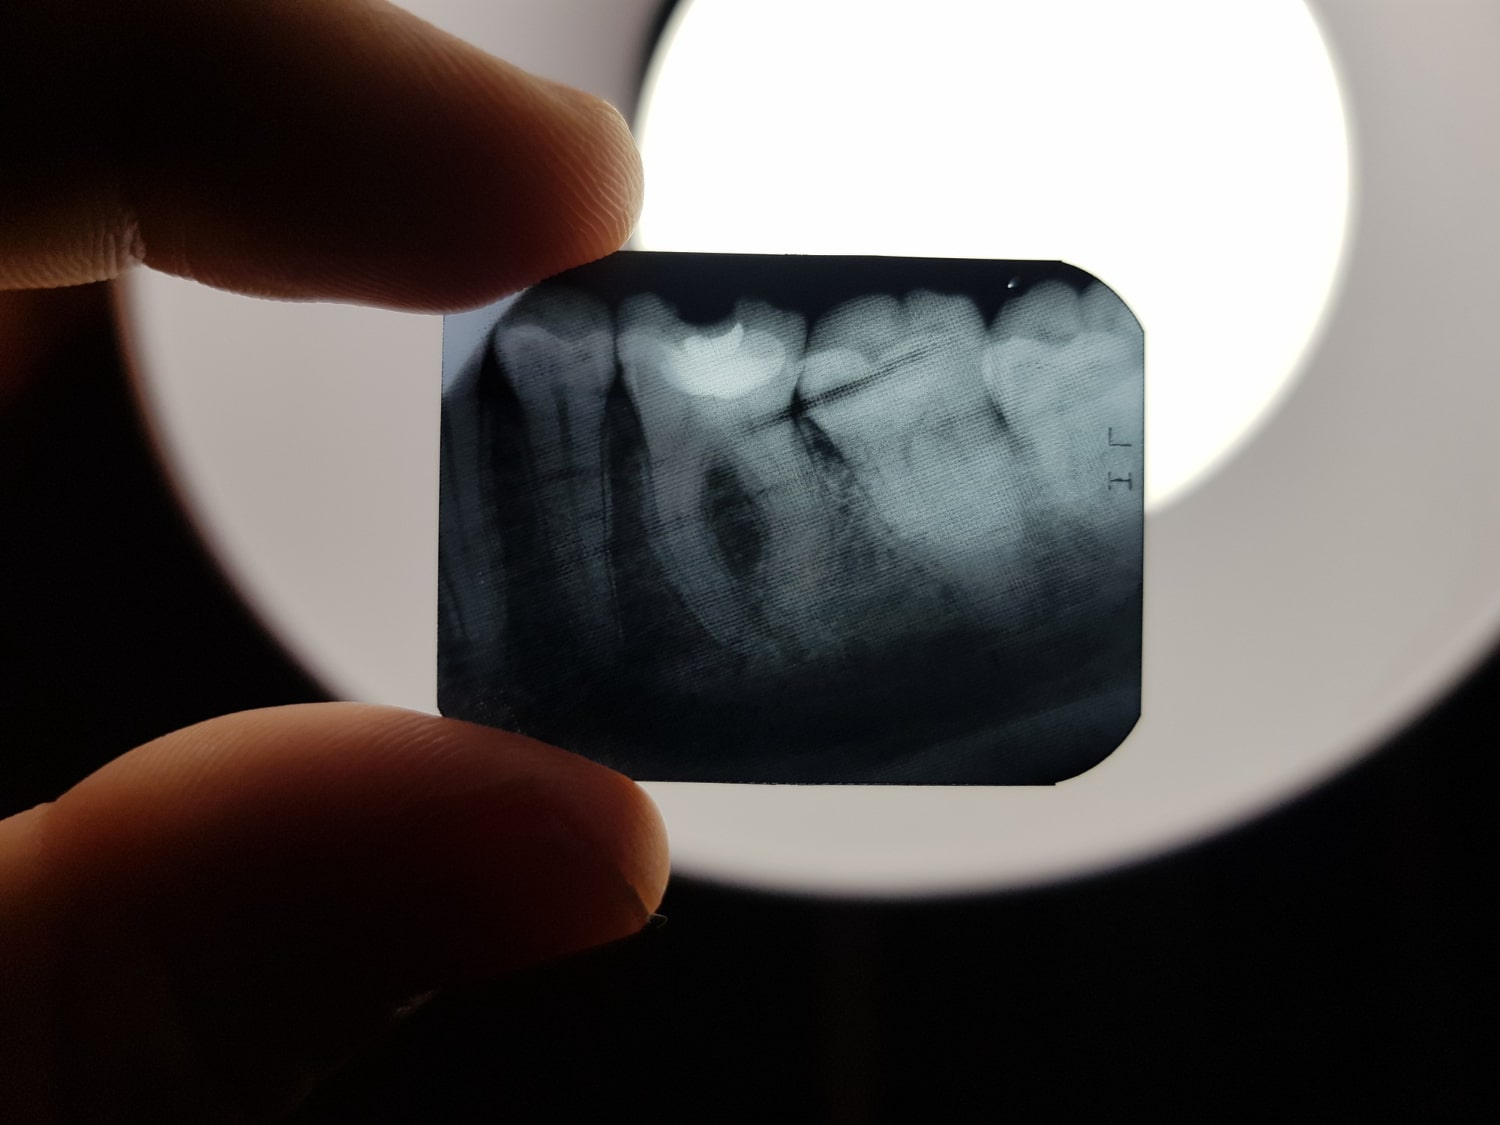

RTG Punktowe

Masz podejrzenie próchnicy, chorób przyzębia lub planujesz leczenie stomatologiczne i potrzebujesz dokładnej diagnostyki? Niezastąpionym rozwiązaniem może być RTG punktowe, czyli precyzyjne badanie obrazowe pozwalające ocenić stan pojedynczego zęba i otaczających go tkanek. Dzięki takiej diagnostyce lekarz stomatolog może szybko i dokładnie określić przyczynę dolegliwości, zaplanować leczenie, a także uniknąć powikłań w przyszłości.

Dlaczego wykonuje się RTG punktowe? Najczęściej w celu wykrycia próchnicy, oceny jakości wypełnień, sprawdzenia szczelności koron i mostów, diagnostyki zmian okołowierzchołkowych czy oceny stanu kości. To również podstawowe badanie w trakcie przygotowania do leczenia kanałowego oraz implantologii.

Na szczęście w moim gabinecie w Gliwicach wykonasz RTG punktowe szybko i wygodnie. Badanie jest krótkie, bezbolesne i całkowicie komfortowe dla pacjenta. Co ważne, sprzęt cyfrowy pozwala znacząco ograniczyć dawkę promieniowania w porównaniu z tradycyjnymi aparatami, zachowując przy tym najwyższą jakość obrazu. Dzięki temu diagnostyka jest precyzyjna, a jednocześnie bezpieczna.